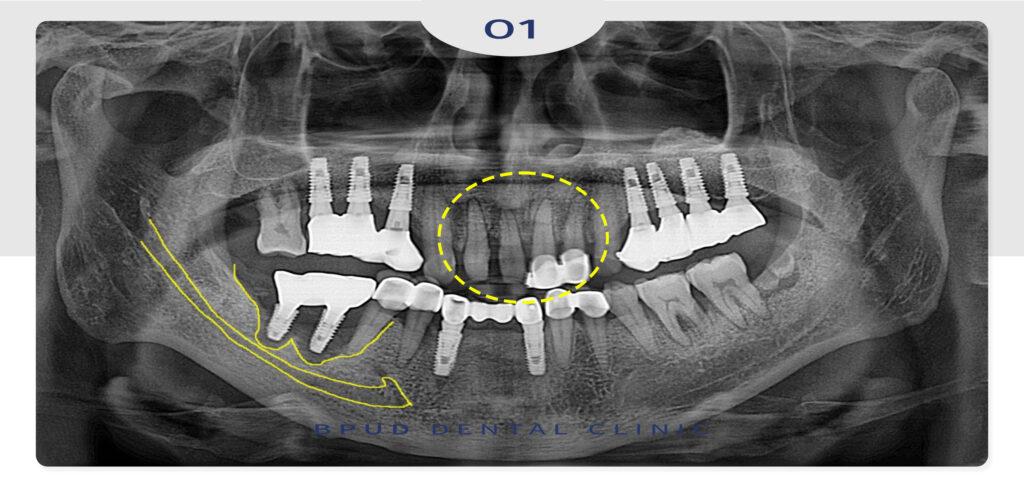

환자분의 처음 내원 당시 파노라마입니다.

임플란트를 하신 갯수는 많았지만

상대적으로 유지 관리가 잘 되어 있는

모습으로 꾸준한 관리를 말씀 드렸었는데요.